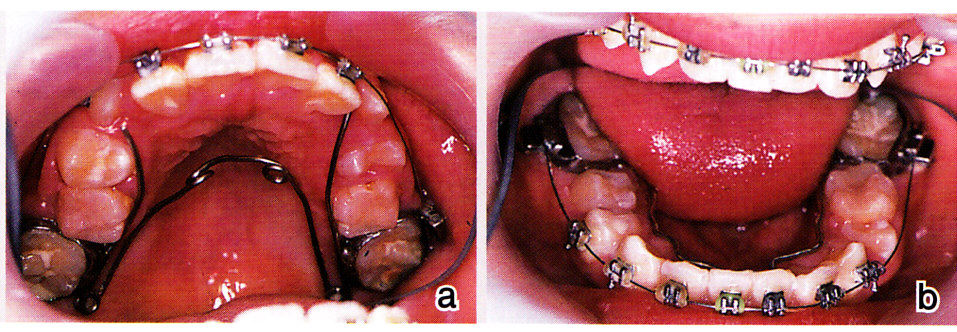

側方歯群の交換時期にはリンガルアーチを装着し、リーウェイスペースを失わないようにしました(図13)。そして、ダイレクトボンドによる歯牙移動を行いました(図14)。混合歯列期における積極的な拡大により、抜歯症例となるのを回避できました(図15)。

図13 a:9歳 側方歯群の交換が始まった。上顎はクワドヘリックスで側方拡大

b:9歳 下顎はリンガルアーチを装着し、リーウェイスペースが失われないようにした

図14 a:10歳 ダイレクトボンディング法による歯牙移動

b:10歳 下顎・・・・リンガルアーチからの距離が側方への拡大量を示している